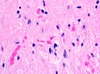

Meningioma Whorling of cells Whorling around an imaginary stem

92

93